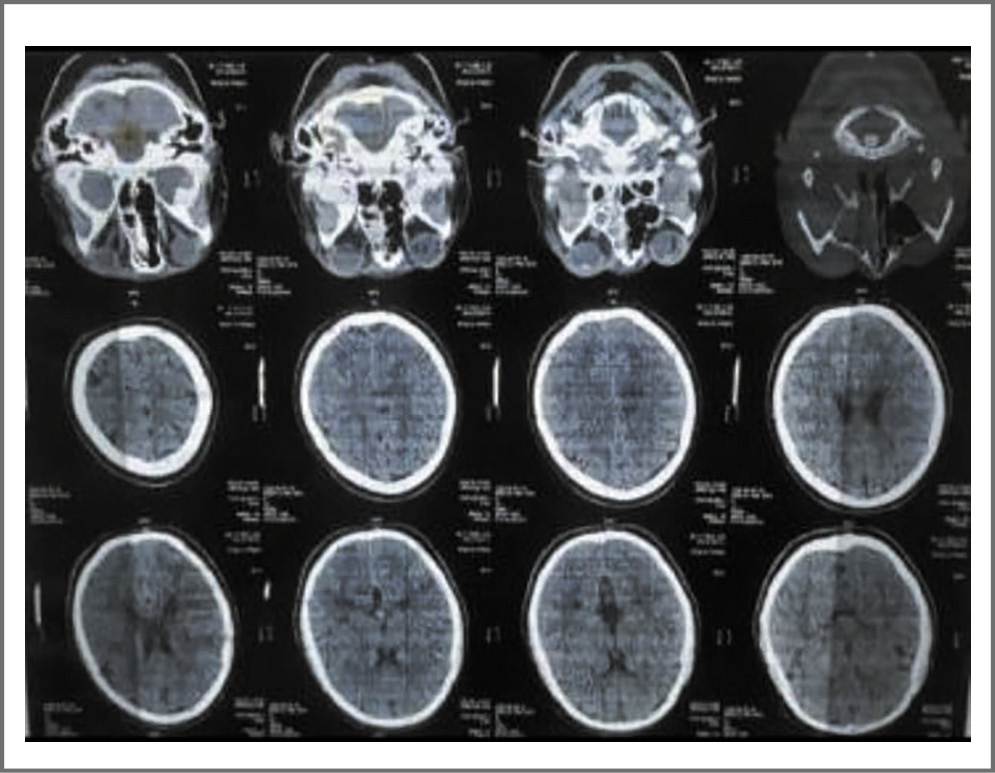

14-й день. КТ головного мозга с болюсным контрастированием. Заключение: отек мягких тканей парабульбарной клетчатки; левосторонний верхнечелюстной синусит; этмоидит; не исключается формирование отека головного мозга (рис. 1).

Рис. 1. КТ головного мозга пациентки Ф. с COVID-19 и мукормикозом: отек мягких тканей парабульбарной клетчатки; левосторонний верхнечелюстной синусит, этмоидит. / Fig. 1. Brain computed tomography scan of the patient F. with COVID-19 and mucormycosis. Edema of soft tissues of peribulbar space. Left-sided maxillary sinusitis, ethmoiditis.

16-й день. КТ головного мозга. Заключение: отек мягких тканей парабульбарной клетчатки; левосторонний верхнечелюстной синусит, этмоидит; ультразвуковое исследование сосудов головного мозга с болюсным контрастированием. Заключение: аневризматические деформации, окклюзии, тромбоз синусов не определяется.